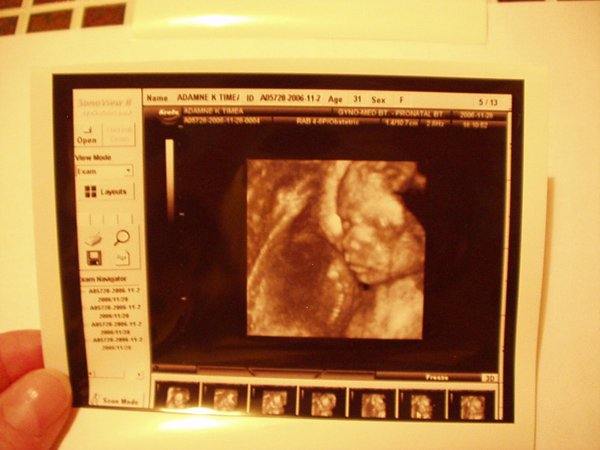

A 17. héten voltunk Pesten 3D-s uh-on Győrfi Mátyásnál a Praxisban. Azt mondta, minden rendben, szépen fejlett kisfiú:):):):)

Most 34 hetes vagyok, és kisfú lesz, Bence. Nem túl nagy baba, de azt mondják szép formás. A méretei inkább 32 hetesnek felelnek meg. Itt van pár kép róla 25+2 hetesen:) (a szeménél a köldökzsinór van! )